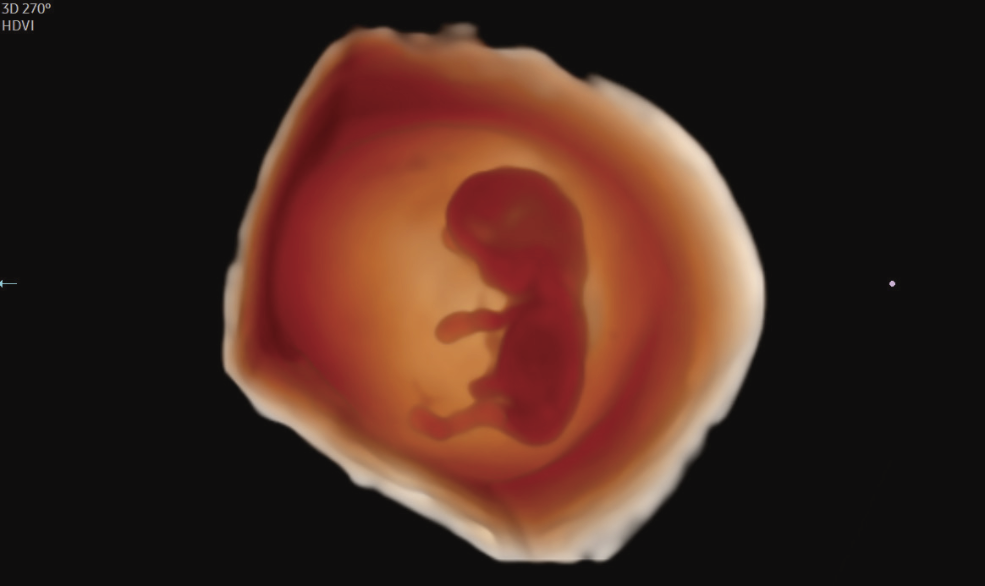

• Recursos exclusivos em 3D: RealisticVue™, CrystalVue™, PortraitVue™, Luminant™.

Imagens Clínicas